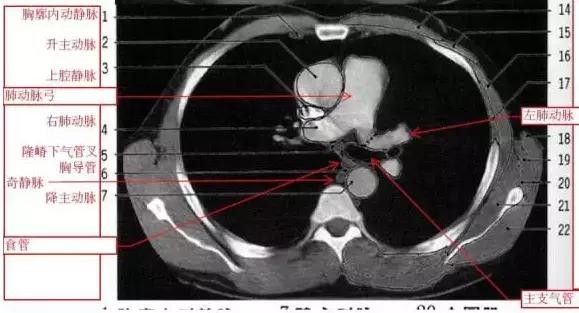

详尽的胸部CT影像示意图

胸部的CT是通过X线计算机体层摄影(CT)对胸部进行检查的一种方法。正常胸部CT层面较多,每一层面结构所表现的图像不同。下面是胸部CT图文示意图,可帮助临床医生详细了解CT结构。我们一起来看一下吧。

来源:影像论坛